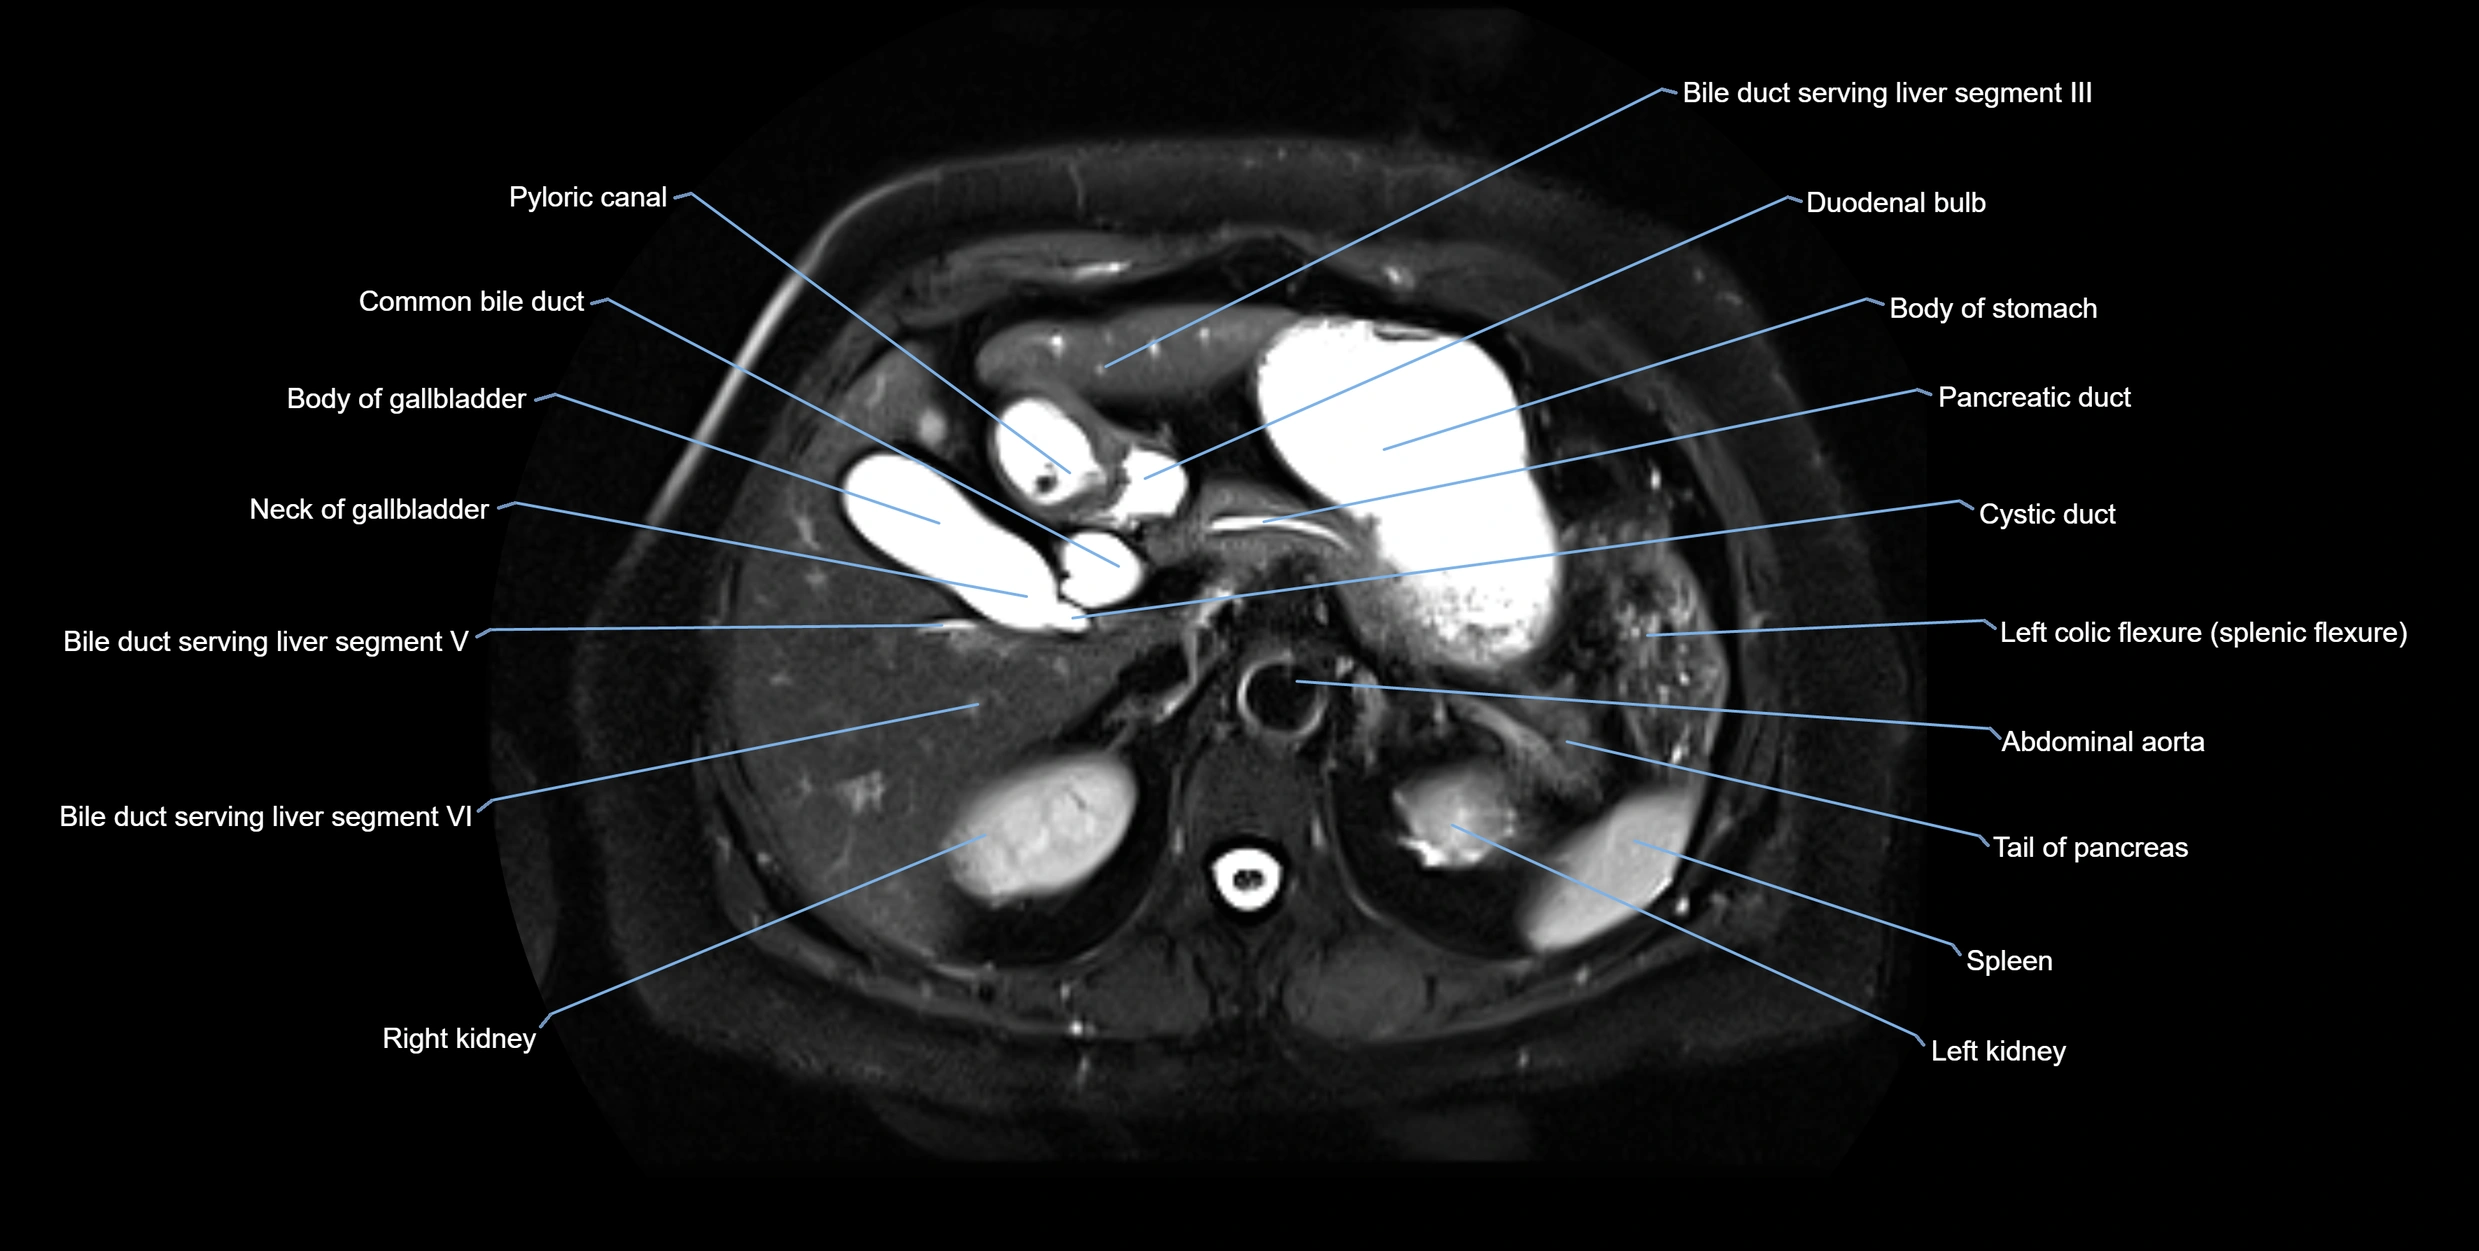

MRI image

image